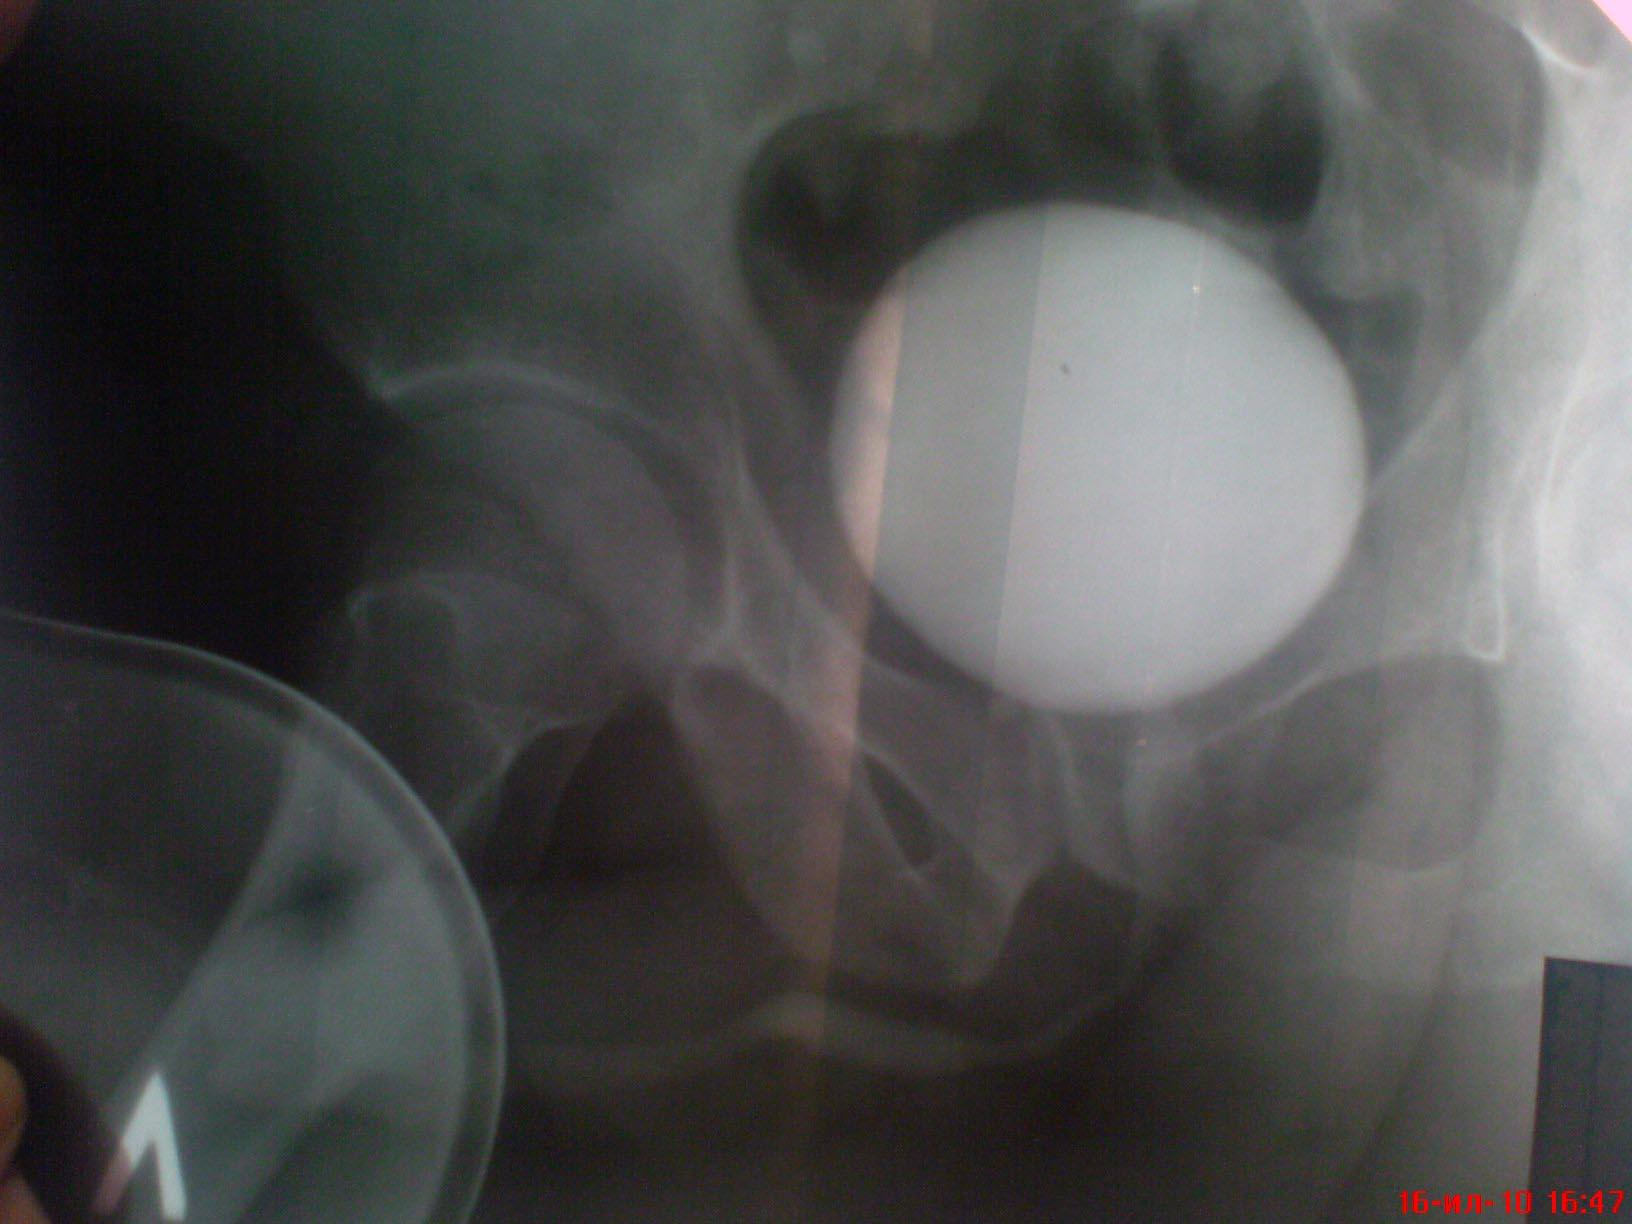

Возможно у Вас проконсультироваться таким образом,я вышлю Вам снимки уретрограмм а Вы скажете свое мнение.